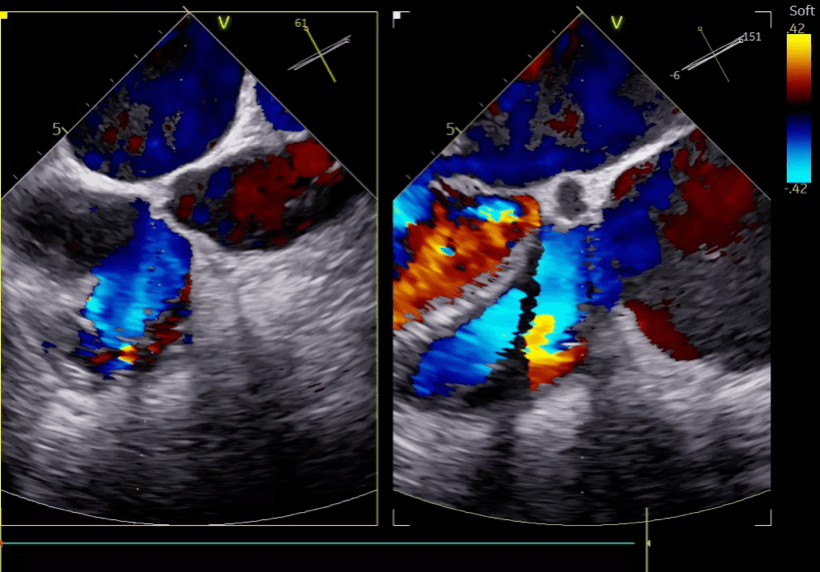

结合术前CT与TEE综合评估,本例患者三尖瓣环严重扩张,反流位置主要集中在前隔瓣叶对合处以及中央处,手术操作难度较高,拟采用两个夹子来缩小瓣环尺寸以改善瓣叶对合,从而降低三尖瓣反流。手术当日,在韩东刚教授精湛的超声技术引导和麻醉团队的密切配合下,邓捷主任、王新宏教授的心脏瓣膜团队术中精准释放两枚K-Clip夹子后,患者三尖瓣瓣环面积明显缩小,瓣叶对合情况显著改善,反流程度由5+降低至2+,成功对严重扩张的三尖瓣瓣环进行了修复和成形。整个手术过程顺利,患者生命体征平稳。

第二枚夹子释放后,三尖瓣反流从术前5+降至2+